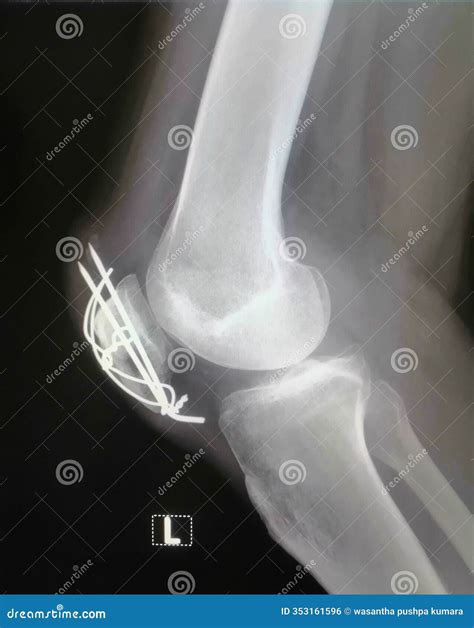

When you arrive at the clinic or hospital, the medical team will likely perform a physical examination followed by diagnostic imaging. An X-ray is the gold standard for identifying fractures, but a CT scan may be required to assess the extent of the damage if the fracture extends into the joint space. Once the extent of the fractured knee symptoms is mapped, the doctor will determine whether non-surgical intervention—such as casting and bracing—or surgical fixation is required.